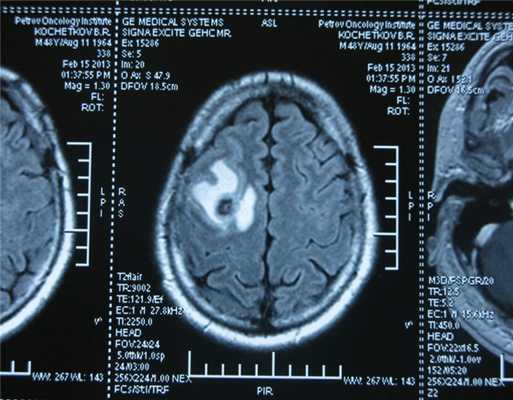

Рисунок 7. - Герминома головного мозга.

- КТ (расшифровка: компьютерная томография), МРТ (расшифровка: магнитно-резонансная томография), ПЭТ-КТ (расшифровка: позитронно-эмиссионная томография, совмещенная с КТ). Эти обследования необходимы, чтобы рассмотреть структуры организма послойно и визуализировать опухоль. Они показывают, как сильно распространен патологический опухолевый процесс на находящиеся рядом ткани и органы, есть ли поражение костей. КТ - это самый чувствительный метод для обнаружения метастазов в легких. Проведение МРТ и КТ головного мозга необходимо, чтобы обнаружить и визуализировать герминогенные новообразования эпифиза.

Также выполняют МРТ головного мозга, чтобы выявить наличие метастазов в нем.

Рисунок 9. - метастаз в головной мозг при герминогенной опухоли.

![Метастаз в головной мозг при герминогенных опухолях (МРТ головного мозга)]()

Метастаз в головной мозг при герминогенных опухолях (МРТ головного мозга)